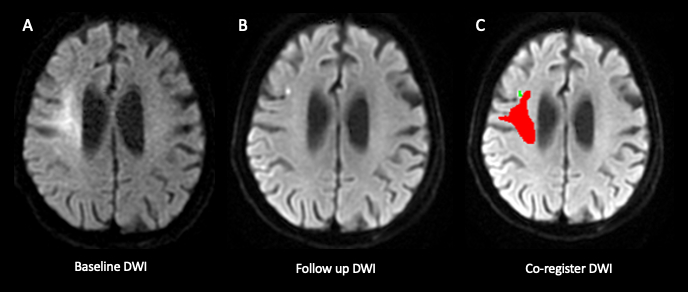

Methods: This retrospective, single-center study included patients with acute large vessel occlusion in the anterior circulation who: (1) underwent MRI within 24 hours of stroke onset, (2) received EVT, and (3) had follow-up MRI within 5 days of EVT from January 2018 to January 2020. Neuroradiologists segmented DWI hyperintense infarcts with ADC hypointensity on pre- and post-EVT MRI, using Fluid-attenuated inversion recovery (FLAIR) sequences to avoid T2 shine-through effects. The DWI/ADC volume ratio was calculated by dividing DWI volume by ADC ≤ 620 × 10-6 mm2/s volume. DWI-ADC mismatch was defined as a DWI/ADC ratio ≥ 2, with no mismatch indicated by a ratio < 2. Final infarct segmentation included hemorrhagic transformation. DWI lesion reversal (DWIR) was defined as the volume of normal-appearing voxels on follow-up DWI but previously hyperintense. DWIR% = (DWIR/baseline DWI volume) × 100 was calculated. We compared demographics, radiological findings, clinical outcomes, and follow-up results between mismatch and no mismatch groups.

Results: Among 73 patients, 20 (27.4%) had DWI-ADC mismatch. Baseline demographics and National Institutes of Health Stroke Scale (NIHSS) were similar between groups. The DWI/ADC ratio was higher in the mismatch group (2.9 vs. 1.5, P < 0.0001). Follow-up lesion volumes and functional outcomes were similar; however, the mismatch group showed a slower infarct growth rate (3.8 ml/h vs. 7.5 ml/h, P = 0.04), a higher likelihood of parent artery stenosis (65% vs. 20.8%, P < 0.001), and increased need for angioplasty or stenting (50% vs. 17%, P < 0.001). The mismatch group also had a higher DWIR% (37.7% vs. 21.2%, P = 0.02).